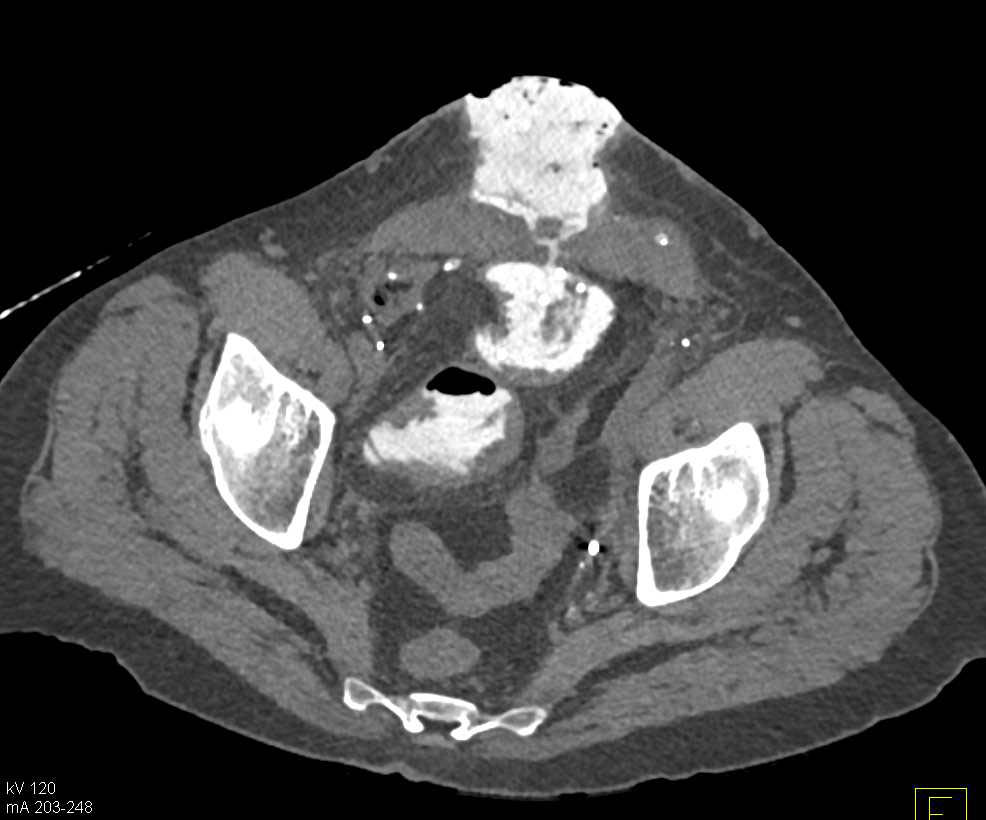

Metastatic Colon Cancer with Liver Metastases and Carcinomatosis